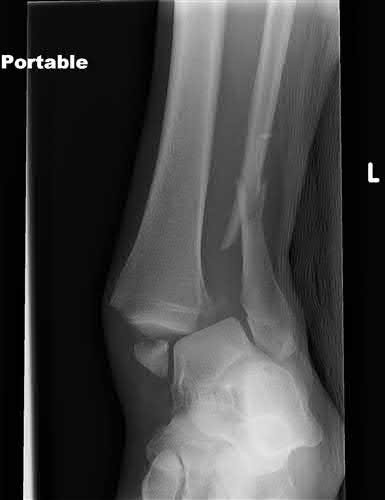

Figures A and B are the Lateral and AP radiographs of a displaced talar neck fracture with tibiotalar dislocation. Figures C and D are the post-reduction sagittal foot CT cuts that reveal a displaced talar neck fracture with medial

comminution.